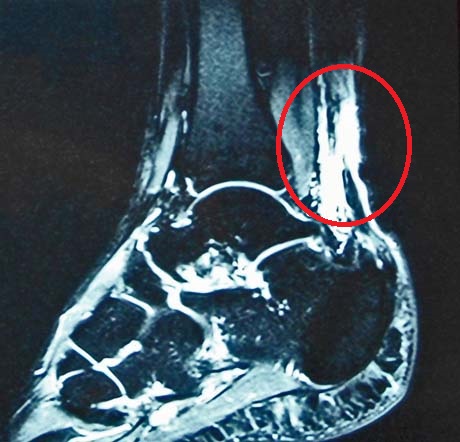

Complete rupture of the Achilles tendon